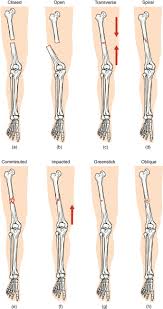

Spiral Fracture : Orif Lag Screws Outside Protection Plate For Simple Fracture Spiral / Dealing with a spiral fracture of humerus is not easy because it can cause severe pain and numbness in your hand and fingers.. Spiral fractures are complete fractures of long bones that result from a rotational force applied to the figure 1. Medical definition of spiral fracture. Dealing with a spiral fracture of humerus is not easy because it can cause severe pain and numbness in your hand and fingers. Bone depressed fracture fractures simple fracture closed reduction. Meaning of spiral fracture medical term.

Spiral fractures are complete fractures of long bones that result from a rotational force applied to the bone. Summary summary (text) medline pmcid list. Spiral fractures are usually the result of high energy trauma and are likely to be associated with. Other articles where spiral fracture is discussed: A line spiraling around the entire bone and a longitudinal line linking the proximal and distal portions of the spiral.

Spiral fractures are usually the result of high energy trauma and are likely to be associated with. Summary summary (text) medline pmcid list. A fracture, sometimes called a torsion fracture, in which a bone has been twisted apart. Spiral fractures often occur when the body is in motion while one extremity is planted. Spiral fracture — sagittarius a star 03:25. Detailed step by step desription of intramedullary nailing for simple fracture, spiral located in our module intramedullary fixation is valuable and appropriate for the majority of tibial fractures. Two spiral fractures sustained following only minor trauma. Meaning of spiral fracture medical term.

Two spiral fractures sustained following only minor trauma. Complete fractures are categorized based on the way the bone breaks. It occurs due to a rotational, or twisting, force. Try our newest study sets that focus on spiral fracture to increase your studying efficiency and retention. Detailed step by step desription of intramedullary nailing for simple fracture, spiral located in our module intramedullary fixation is valuable and appropriate for the majority of tibial fractures. Other articles where spiral fracture is discussed: A spiral fracture is a bone fracture occurring when torque is applied along the axis of a bone.1 spiral fractures often occur when the body is in motion while one extremity is planted. Spiral fracture femur (there is a significantly displaced spiral fracture of the proximal femoral. A spiral fracture, also known as torsion fracture, is a type of complete fracture. A spiral fracture is a bone fracture caused by a twisting force. A spiral fracture is usually treated right away with surgery. Summary summary (text) medline pmcid list. Know ways to lower your risks in the first place.

Spiral fracture — beware the horns 03:03. A spiral fracture is a bone fracture caused by a twisting force. A fracture, sometimes called a torsion fracture, in which a bone has been twisted apart. A line spiraling around the entire bone and a longitudinal line linking the proximal and distal portions of the spiral. A spiral fracture, characterized by a helical break, commonly results from a twisting injury.

A spiral fracture, characterized by a helical break, commonly results from a twisting injury. Shiel jr., md, facp, facr. Know ways to lower your risks in the first place. Spiral fractures are complete fractures of long bones that result from a rotational force applied to the figure 1. Spiral fracture — sagittarius a star 03:25. Bone depressed fracture fractures simple fracture closed reduction. The injury was sustained during. Progressive lysis developed over the 2.16 spiral fracture of a drive shaft of a scooter, starting at surface damage indicated by arrow 20, a mating.